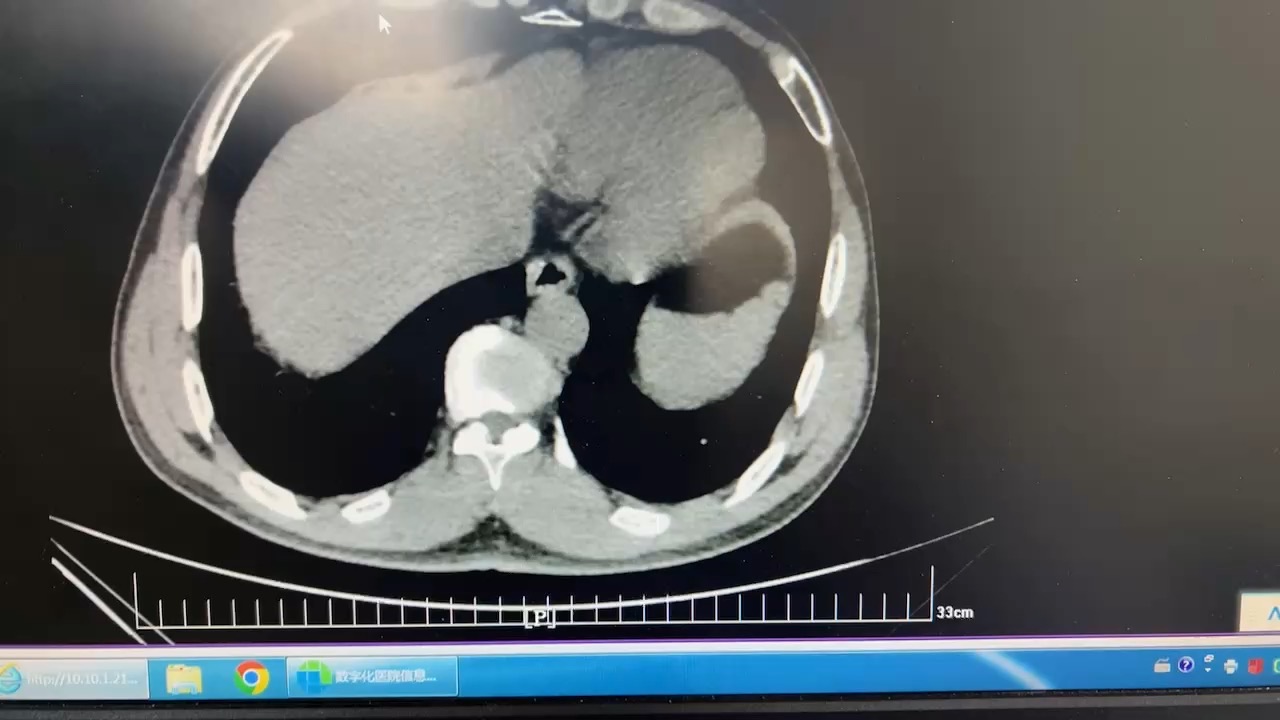

鹿角形结石你见过吗?这样的结石如何治疗?

现病史:患者2周前无明显诱因出现左侧腰腹部疼痛,行泌尿系超声示:1.双肾囊肿;2.左肾结石(多发);3前列腺增生伴钙化。今为进一步诊治,来我院,门诊以“左侧肾结石、前列腺增生、双侧单纯性肾囊肿”患者精神饮食睡眠尚可,大便正常。尿常规:白细胞(3+),硝酸盐(+),尿培养大肠埃希菌,耐药。